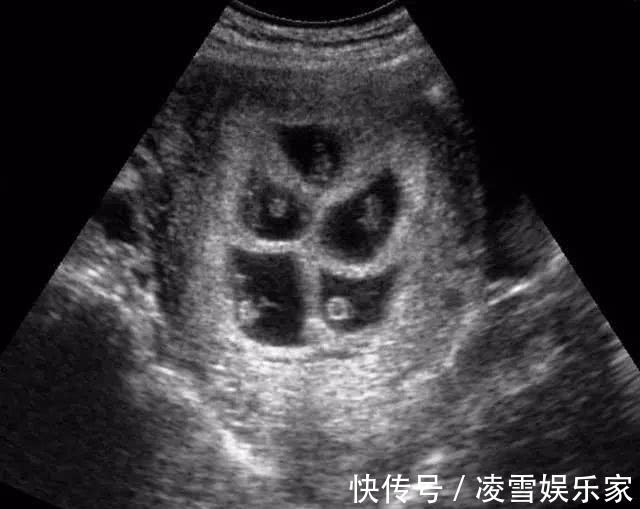

莉莉今年25岁,和老公是大学同学,两人毕业后就领证结婚了。婚后没多久,莉莉就欣喜地发现自己怀孕了,婆家人得知莉莉怀孕的消息都高兴极了,赶紧带着莉莉去医院做检查,经过检查,莉莉的确怀孕了,让一家子乐坏了。在怀孕第三个月时,莉莉的孕肚就比其他孕妇要大上一圈,婆婆还调侃莉莉怀的是双胞胎。去医院做产检后,医生惊讶的发现莉莉肚子里竟然有6个胎心,这也就是说莉莉怀了6胞胎!!听到医生的话后,婆婆和莉莉都被吓了一跳,原本以为怀的是双胞胎,却没成想怀的是6胞胎。

因为怀多胞胎的风险比较大,所以医生建议莉莉减胎。但莉莉并不愿意减胎,她觉得每一个孩子都是上天赐给她的礼物,都是自己的亲骨肉,无论舍弃哪一个孩子,都舍不得。经过和家里人的商量,全家人一致决定留下全部的孩子。在怀孕5个多月时,莉莉的肚子就已经大的走不动路了,双脚也出现了严重的浮肿。好在婆婆和老公都对莉莉照顾有加,这让她感到很欣慰。到第七个月时,医生就告诉莉莉要提前剖腹产了。

手术当天,产科医生就来了20多位,经过3个多小时的剖腹产手术,莉莉平安产下了6名可爱的宝宝。当医生看到孩子的性别后,不禁感叹道:“这才是真正的金六福啊。”原来莉莉生下了3男3女,一共3对龙凤胎